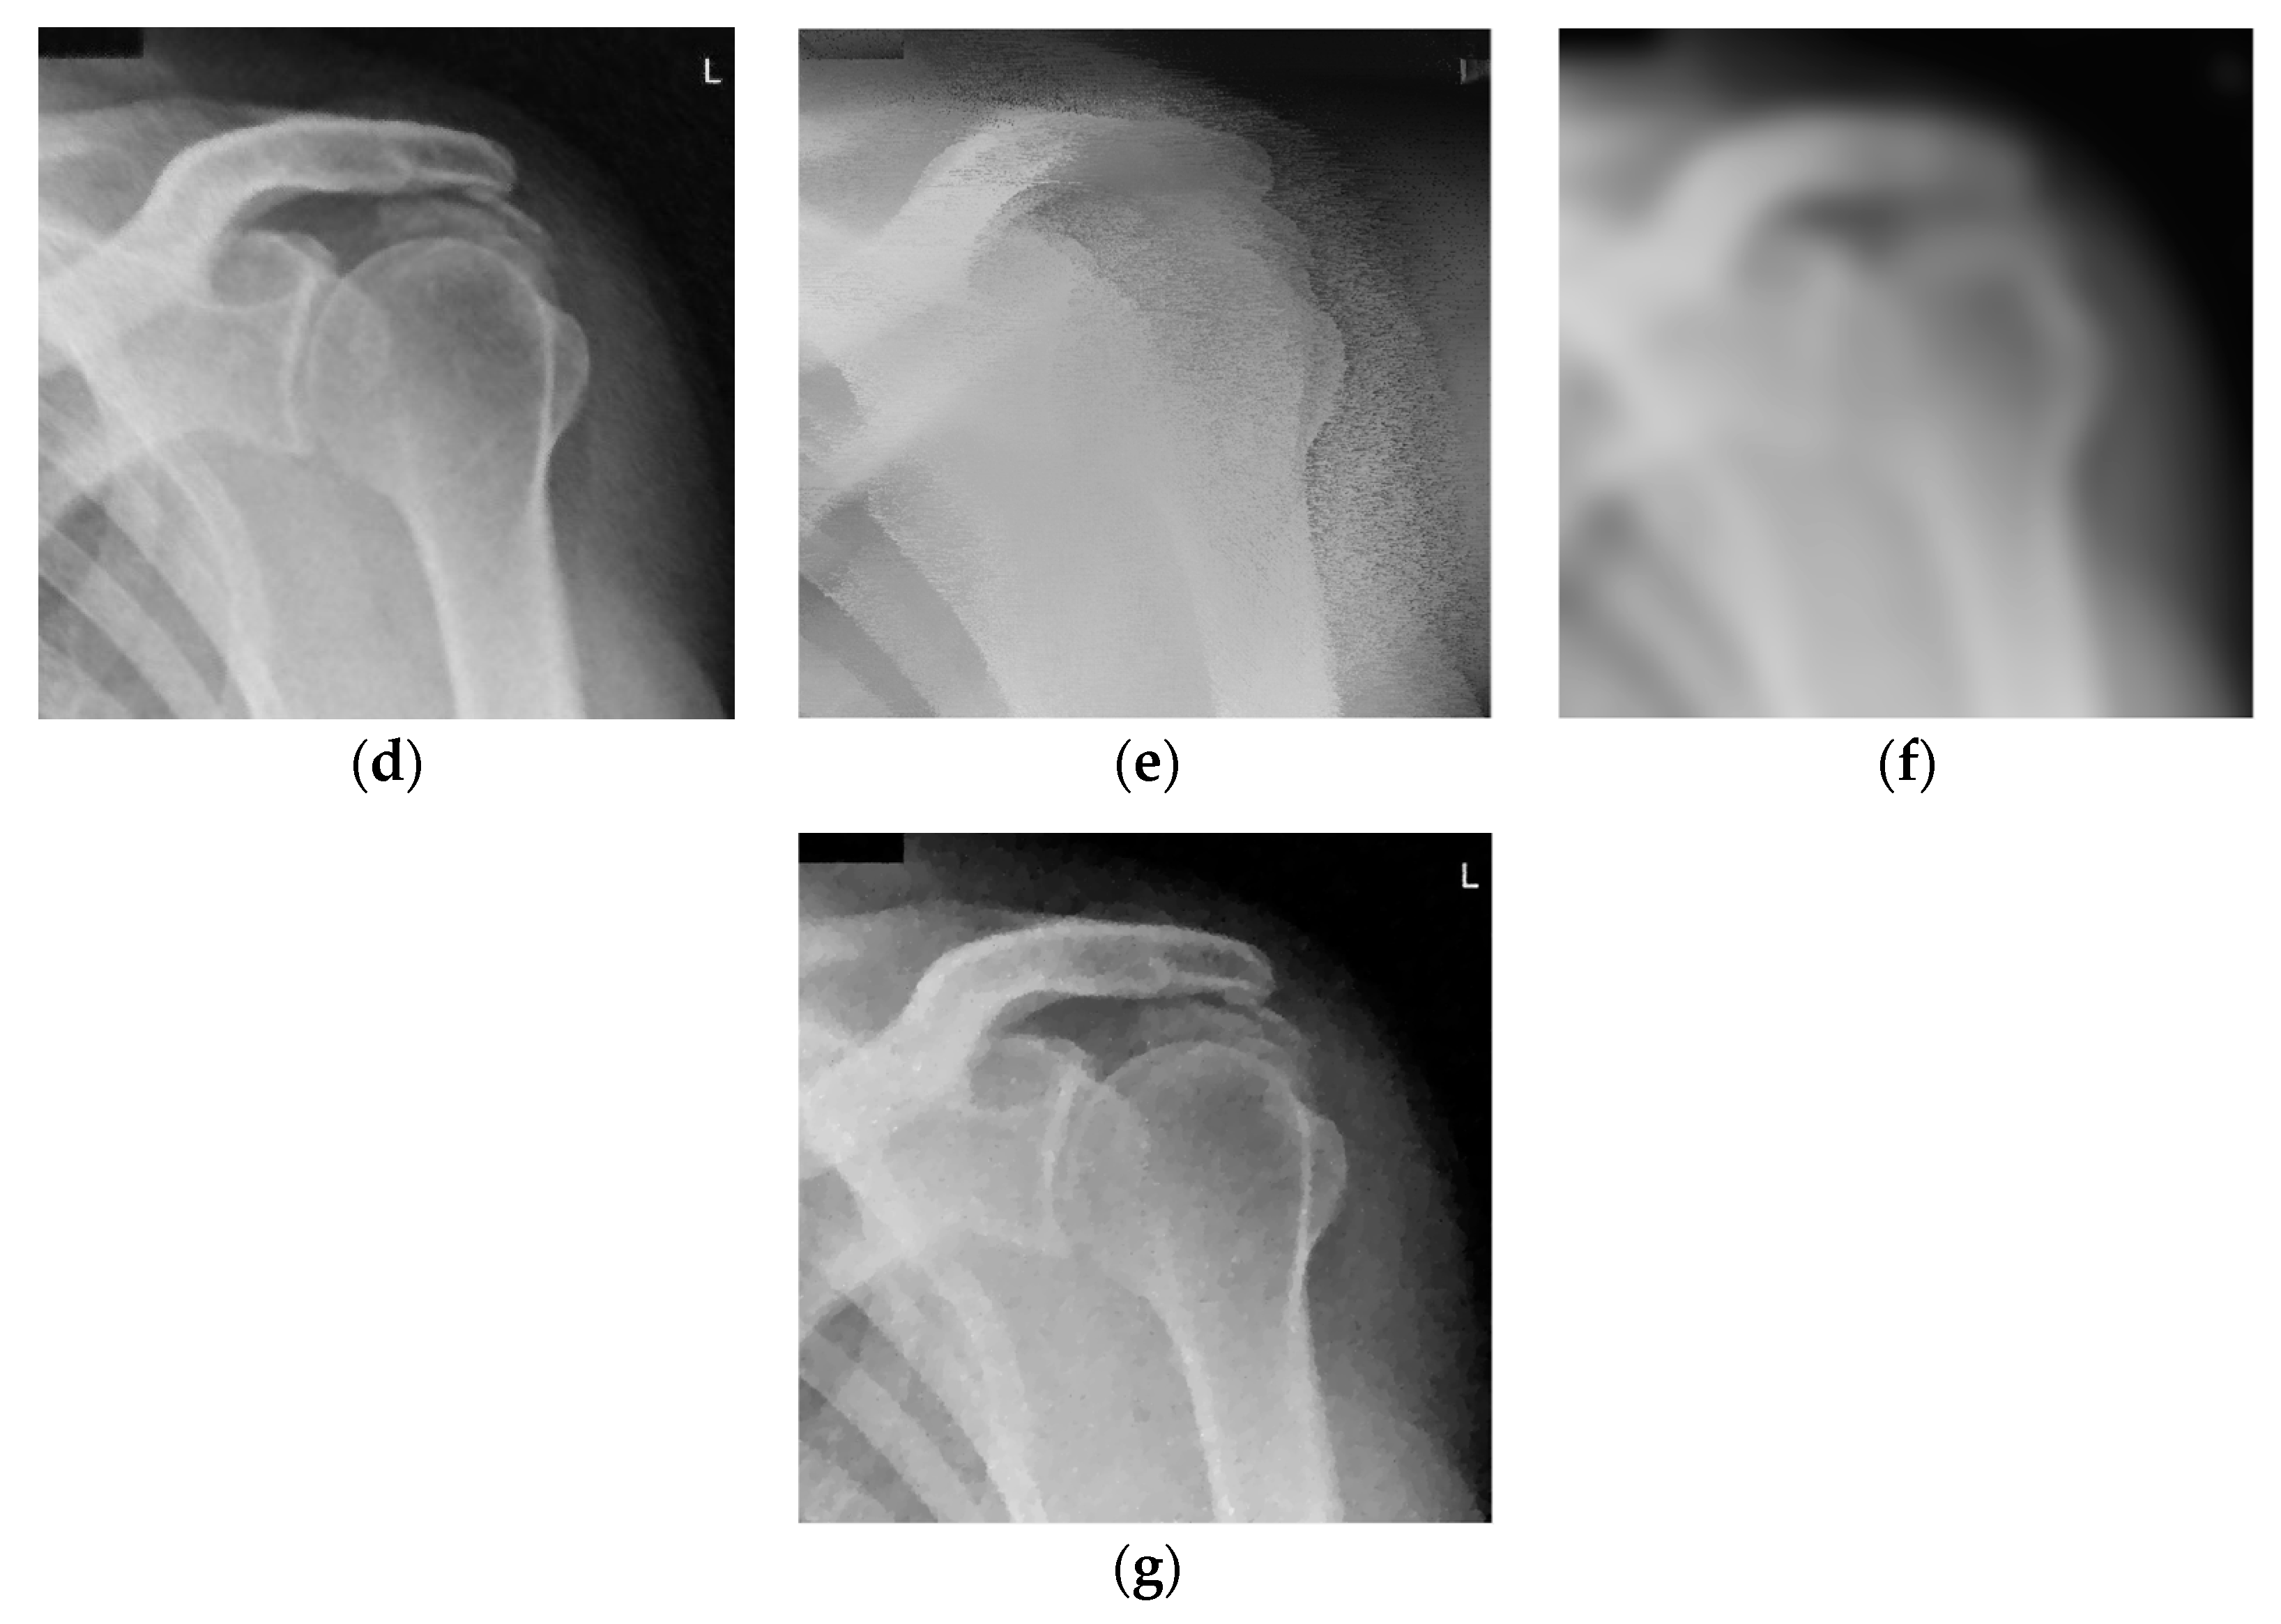

Shoulder X-ray images (with resolution 1024 × 1018) are presented in Figure 3. Namely, the noise-free image is given in Figure 3a. The noisy image is shown in Figure 3b (corrupted by additive white Gaussian noise (AWGN) the standard deviation of which is σ = 25). Figure 3c–e present images denoised using the RICI based method. Namely, Figure 3c is denoised using the quadrilateral regions, Figure 3d is denoised using the octagonal regions and Figure 3e is denoised using the hexadecagonal regions.

Figure 3.

Shoulder X-ray scan. (a) Original noise-free image; (b) Noisy image (AWGN with σ = 25); (c) Image denoised using the 2D LPA-RICI method (quadrilateral region, Г = 1.8, Rc = 0.8); (d) Image denoised using the 2D LPA-RICI method (octagonal region, Г = 1.8, Rc = 0.8); (e) Image denoised using the 2D LPA-RICI method (hexadecagonal region, Г = 1.8, Rc = 0.8); (f) Image denoised using Gaussian smoothing filters; (g) Image denoised using total variation denoising.

Denosing results, in terms of the PSNR, for the shoulder X-ray image are given in Table 1 (for various Г and Rc values). The first column gives regions (octagonal, octagonal and hexadecagonal, respectively). The second and the third column present parameter values for the 2D LPA-RICI denoising method. The fourth column presents the standard deviation of the AWGN. The fifth column provides the noisy image PSNR followed by the column giving the PSNR for image denoised using the proposed RICI based method. The last three columns of the Table 1 show the PSNRs of the images denoised using fixed size filtering (2D median filter), Gaussian smoothing filters and total variation denoising, respectively. For the Gaussian smoothing filtering a Matlab function imgaussfilt was used with standard deviation values chosen same as the standard deviations of the AWGN (σ = 20, 25 and 30). For the total variation denoising [12] Matlab function provided at the MathWorks was used with parameter λ chosen as λ = 0.2, λ = 0.25 and λ = 0.3 for the three tested AWGN levels (σ = 20, 25 and 30), respectively.

Table 2 gives PSNR improvements obtained using the 2D LPA-RICI method vs. noisy image and images denoised using the fixed size filtering, Gaussian smoothing filters and total variation method, respectively. As shown in Table 2, the proposed adaptive RICI based method outperforms the fixed size filters in all cases. Furthermore, it outperforms Gaussian smoothing filters and total variation denoising when quadrilateral and octagonal regions are used (hexadecagonal regions do not outperform Gaussian smoothing and total variation denoising methods).

Namely, the 2D LPA-RICI with quadrilateral regions increased the PSNR of the denoised image by up to 9.13 dB, with octagonal regions increased the PSNR by up to 10.50 dB and with hexadecagonal regions increased the PSNR by up to 4.69 dB (when compared to the noisy image). Also, the proposed 2D LPA-RICI method outperformed the fixed size 2D median filtering by up to 7.99 dB, the Gaussian smoothing filters by up to 6.08 dB and the total variation denoising by up to 4.35 dB for shoulder X-ray scan.